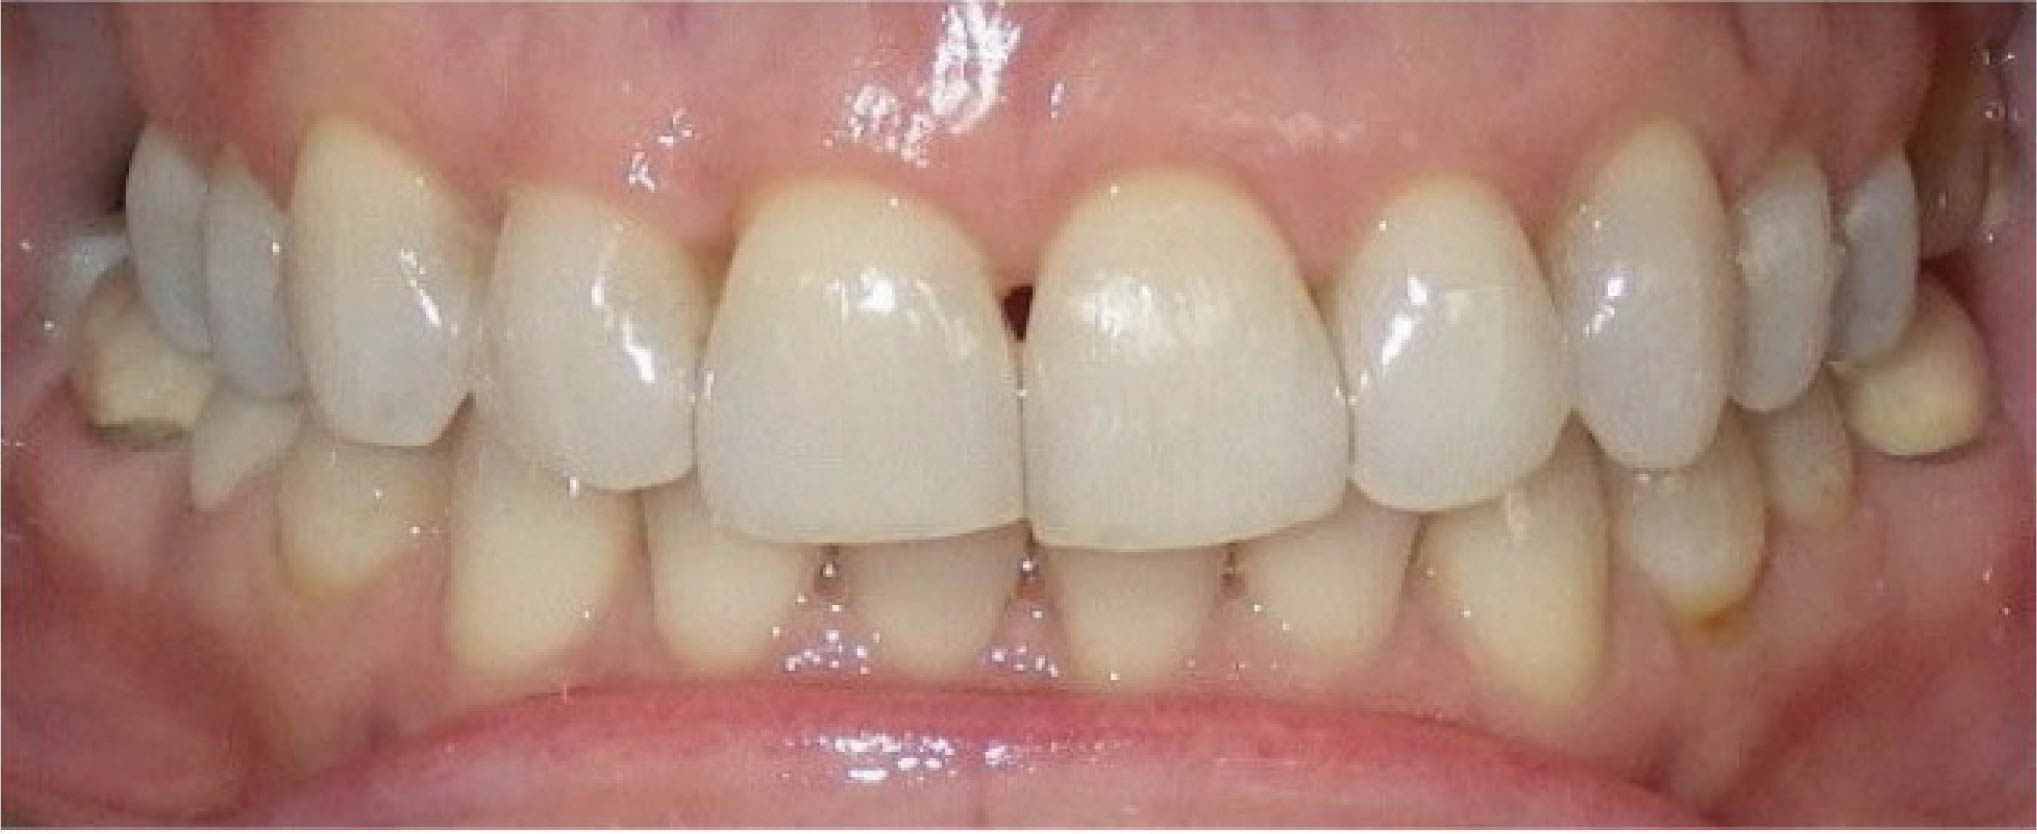

: اصلاح اورجت

سومین کاربرد استریپ اصلاح اورجت در بیماران کلاسII یا III است. اکلوژن بیمار شکل 147-6 کلاسIII است. در این بیمار از پایین استریپ کردیم تا با حرکت خلفی قدامیها به اورجت مطلوب و رابطه کانینی کلاسI برسیم. البته در این بیمار از الاستیک کلاسIII هم استفاده گردیده است. استریپ خلفی در هر دو سمت انجام گردید.

نتایج درمان در شکل 149-6 مشخص است.

شکل 147-6

شکل 148-6

شکل 149-6